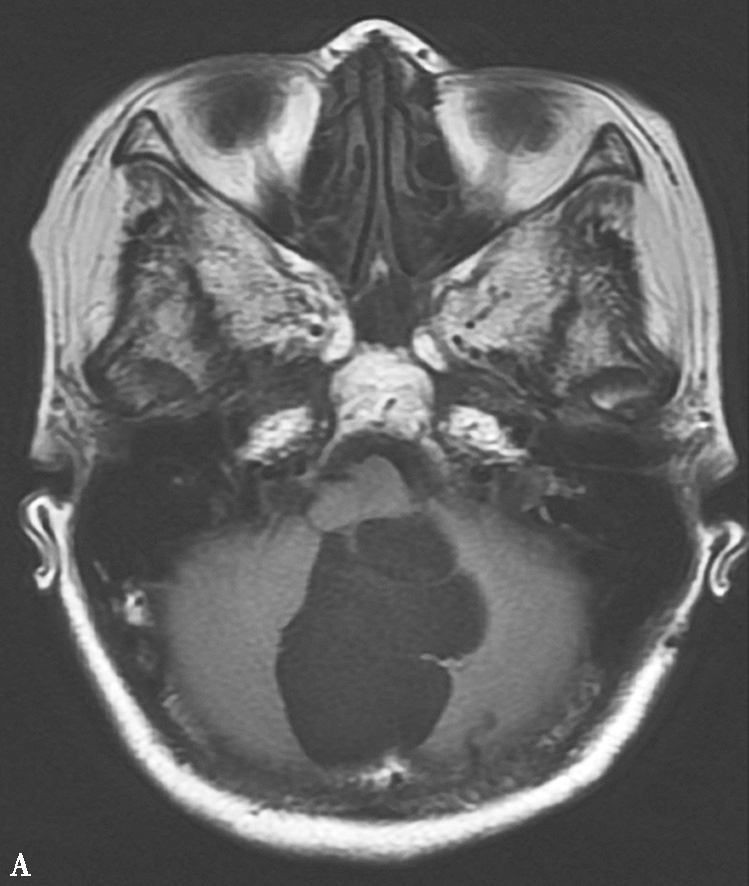

图1-12 血管母细胞瘤

A.MRI T 1 WI横轴位;B.T 1 WI横轴位

图1-12 血管母细胞瘤(续)

C.T 2 WI矢状位;D.T 1 WI增强,示小脑蚓部见一囊性肿块,其内囊液呈长T 1 、长T 2 液性信号,囊壁有卵圆形等信号结节,呈“大囊伴小附壁结节”表现,增强扫描壁结节显著强化,囊壁不强化